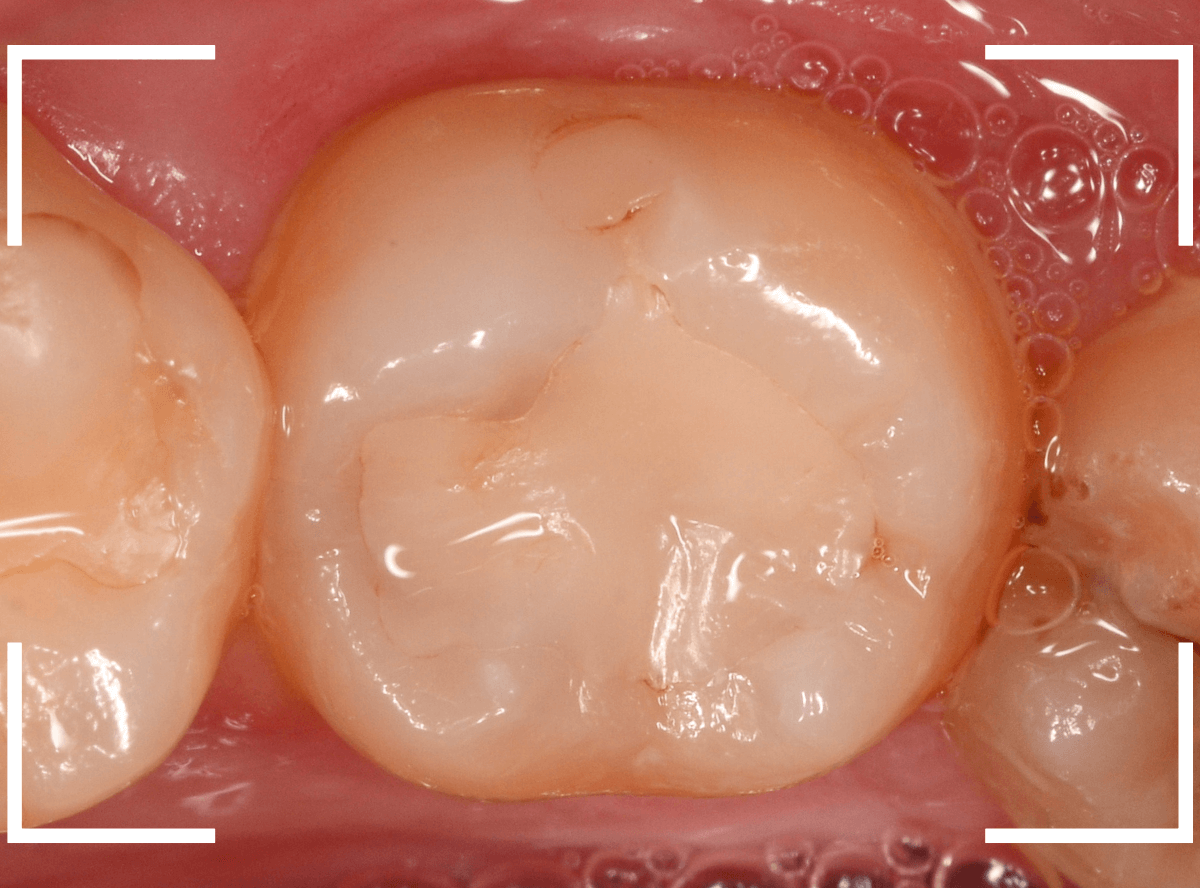

Case.15 下の奥歯がたまに痛い

メンテナンス中に、「下の奥歯がたまに痛い」という訴えをされた患者さんです。

「奥歯がたまに痛いけど、どの歯かははっきりわからない」という事で、Case.15のように、打診をしてもどの歯も特に反応もありませんでしたが、レジンの中の虫歯が怪しい歯がありました。

レントゲン写真で確認します。

あまりはっきりしませんが、レジンの下で虫歯がありそうな感じです。

レジンを外して中を調べます。

それほど深くはありませんでしたが、レジンの中で虫歯が進行しはじめていました。

全ての虫歯を除去したところです。

レジンをつめ直して治療終了です。

おそらくこれで症状は改善されるでしょう。

「たまに痛い」など、症状がハッキリしない場合は、原因も見つけづらい事が多いです。

今回は、レントゲン写真から原因が推察できましたので、良かったです。